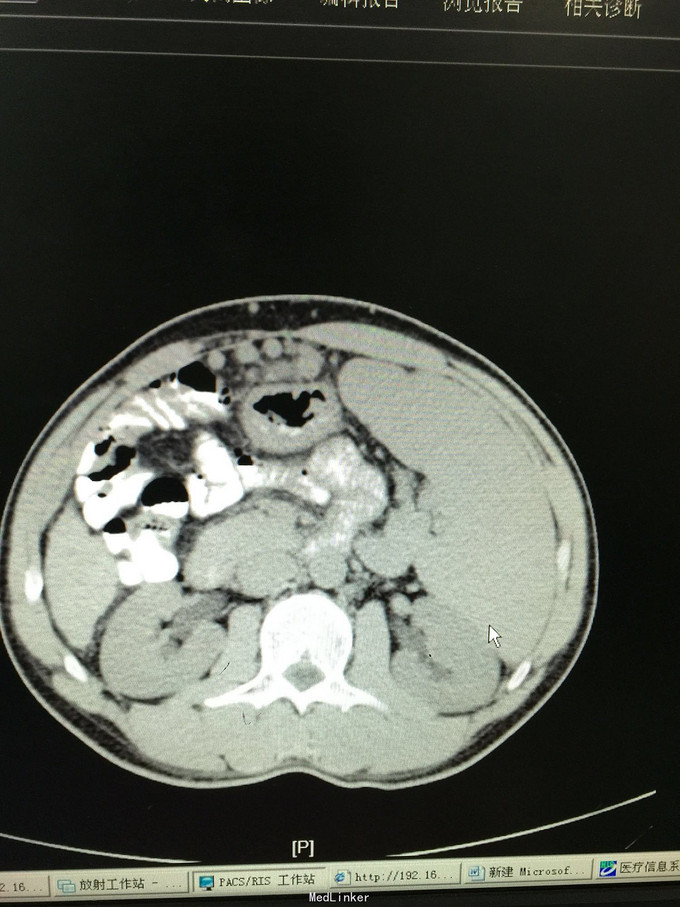

42岁男患,转移性右下腹痛5天为主诉入院。 患者5天前无明显诱因出现中上腹部疼痛,继而转移为右下腹部疼痛,呈持续性绞痛,发热最高体温38.4摄氏度,无恶心呕吐,无寒战,排气排便正常,自行给予口服抗炎药物治疗后发热缓解,腹部疼痛症状缓解不明显,并有加重趋势来诊。门诊查彩超示阑尾炎伴周围脓肿,并收入院治疗。既往发现乙型肝炎肝硬化3年。家族遗传性乙肝

查体:各生命体征正常,心肺无异常,腹部查体:腹平坦,未见腹壁静脉曲张,腹软,未见胃肠型及蠕动波,右下腹可触及一质韧包块,大小约5✖️3cm,界限欠清,活动度一般,右下腹压痛阳性,反跳痛弱阳性,无肌紧张,以麦氏点压痛为重。 辅助检查:详见图片

诊断:急性阑尾炎伴阑尾周围脓肿,乙肝肝硬化 处理:患者入院后经查无腹膜炎体征,经上级医师查看后指示患者阑尾炎伴周围脓肿形成,存在手术相对禁忌,无手术绝对指证,建议给予积极抗炎对症治疗,患者肝炎肝硬化,注意各理化指标变化,积极复查。